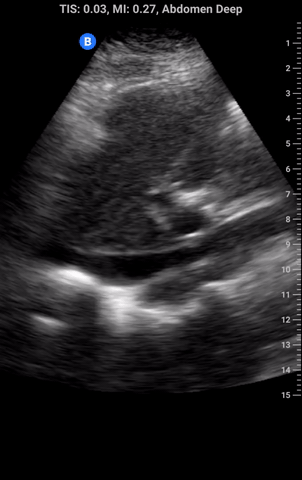

The IVC can be imaged from 2 places: the epigastrium (left) or R4 zone (right). We consider R4 a “rescue view” to be used when the epigastric is not accessible and to be used with caution as it is a non-standard view.

Begin in transverse; you should see the left lobe of the liver below this 2 tubular structures (IVC and aorta) and the spine below. Center the IVC and then rotate to the longitudinal view.